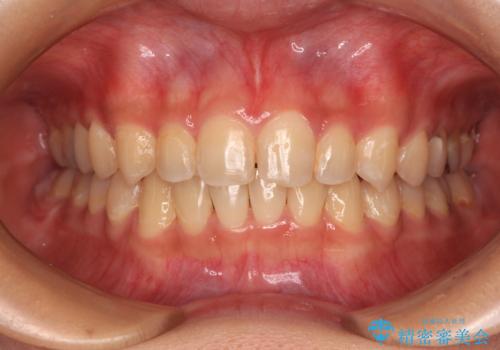

前歯のデコボコを整える インビザラインによる矯正治療

担当医 藤巻太一朗